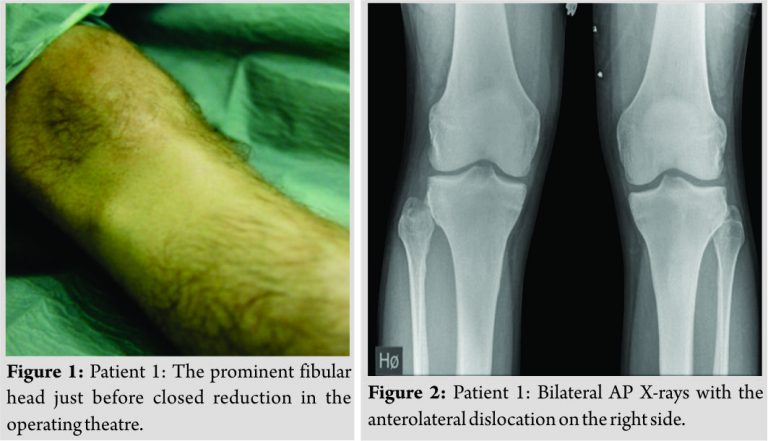

Case Reports: Case 1: A 25-year-old man fell in a football match. He had pain in his leg especially proximally. There was a prominent fibular head on inspection. X-rays showed an anterolateral dislocation in the proximal tibiofibular joint. The dislocation was treated by closed reduction under spinal anesthesia. The joint was stable when tested subsequently. He avoided weight bearing for 2 weeks. At 6 months follow-up, the patient played football at the same level.

Patient 1

A 25-year-old man had a fall during a football match where his right leg was trapped under his body. He had pain over the ankle and especially proximally in the leg. Inspection revealed a prominent fibular head (Fig. 1). Stability testing of the right knee showed no instability and the peroneal nerve was intact. X-rays (of both legs/knees) showed an anterolateral dislocation in the proximal tibiofibular joint (Fig. 2). The dislocation was treated with closed reduction under spinal anesthesia. The joint was then stable when tested. He avoided weight bearing for 2 weeks. At 6 months follow-up, the patient played football at the same level as before the injury.

A traumatic dislocation of the tibiofibular joint is an uncommon injury, comprising <1% of all knee injuries [4]. Anterolateral dislocations are most common (85%), followed by posteromedial (10%) ,and superior (2%) [5].The literature has mentioned about 140 cases (108 +30) from its first description in 1874 until 2014 [1,4]. They are mostly related to sporting activities [6]. Left untreated, the patient may experience chronic pain and instability in the knee, abnormal gait and reduced sporting performance [7]. Injury to the common peroneal nerve (transient) is rarely (5%) seen especially in posteromedial dislocations [3,8]. A high index of suspicion is required in traumas with lateral knee symptoms and inability to bear weight. The mechanism of the injury and adequate physical examination will lead to right diagnosis. Bilateral AP X-rays (as in our patient 1) may be helpful, but the best option is to perform a CT scan (or magnetic resonance imaging) as we did in our patient 2. The function of the common peroneal nerve should be noted. The best treatment in an acute setting is not known yet. There is some agreement that the initial management of an acute traumatic anterolateral dislocation should be closed reduction (direct posterior pressure to the dislocated fibular head with the knee in (full) flexion and the foot externally rotated, in dorsiflexion and everted) [9]. Others recommend immediate mobilization with the intention to provoke spontaneous reduction [10]. We used spinal anesthesia in our patient 1, but one could try to reduce the dislocation first under local anesthesia in combination with muscle relaxation. This failed in our patient 2. There is no consensus as to the method or duration of immobilization or the weight-bearing status following closed reduction [4,9]. There is at present no clear evidence for restriction of weight bearing or immobilization after a successful closed or spontaneous reduction [4]. We did not use anyspecific post reduction rehabilitation protocol. Open reduction (with primary repair of the ligament structures) and (temporary) fixation are required if the closed reduction fails [9]. In an acute setting of joint instability after closed reduction, the most common surgery described is also open reduction combined with (temporary) fixation [11]. There is also no consensus as to the method and the duration of the temporary fixation. This varies between Kirschnerwire(s), pin(s), or screw(s) for 3–26 weeks in the literature [4,11]. In our patient 3, we chose one-screw fixation for 6 weeks, with full range of motion in the knee and full restriction of weight bearing as long as the screw was in place, which we thought was a reasonable protocol based on the existing literature. We have no reason to believe that the residual symptoms in patient 3 were caused by our setup. We have a recorded 6 months follow-up of all three patients. After several years, none of these patients contacted our department/hospital, the only in the region treating these conditions. We have therefore reason to believe that there is no changing or worsening of the patients’ complaints after this first 6 months follow-up.